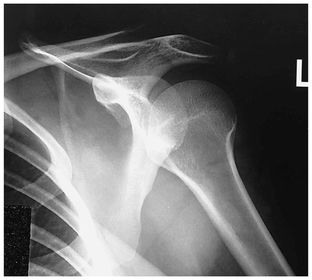

Which projection/position is this? Transthoracic Shoulder ___________________ ribs are blurred out from orthostatic breathing